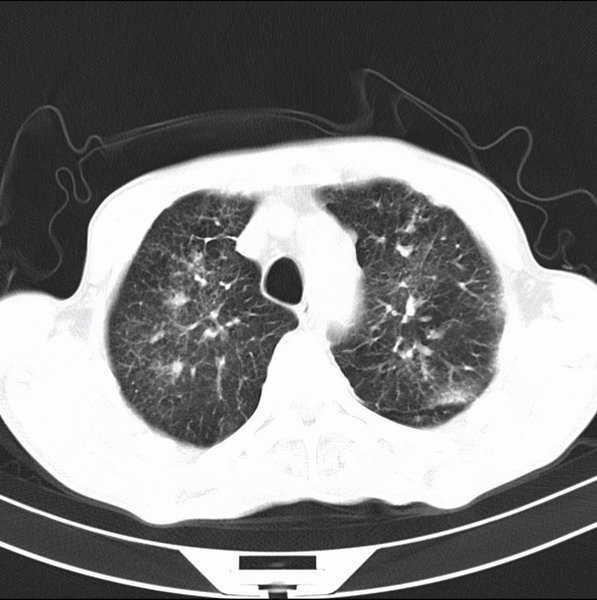

炎性并间质纤维化

炎性并间质纤维化,请询问病史,如用过平阳霉素或其他化疗药.可能为药物引起的间质纤维化.